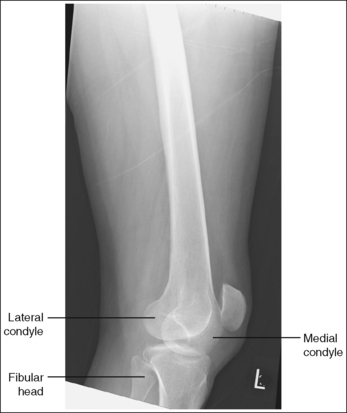

The lower leg demonstrates a lateral projection. The distal fibula is superimposed by the posterior half of the distal tibia. The fibular midshaft is free of tibial superimposition. The tibia is partially superimposed over the fibular head, and the medial femoral condyle is demonstrated posterior to the lateral condyle if the leg is extended; the condyles are superimposed if the knee is flexed at least 30 degrees (compare Figure 6-67 and Image 51).

• To obtain a lateral lower leg projection, begin by placing the patient in a supine position with the leg extended and the foot dorsiflexed until it forms a 90-degree angle with the lower leg. Next, rotate the leg, positioning the lateral foot surface against the IR and the femoral epicondyles perpendicular to the IR (Figure 6-69).

• Detecting leg rotation. If the distal lower leg was not placed in a lateral projection, the tibiofibular relationship is altered. If the patient's leg was externally rotated (patella positioned too close to the IR and heel elevated off the IR), the distal fibula is situated too far posterior on the tibia, and the fibular head is demonstrated free of tibial superimposition (see Image 52). If the patient's leg was internally rotated (patella positioned too far away from IR and forefoot elevated off the IR), the distal fibula is situated too far anterior on the tibia and fibular head and neck, and possibly the midshaft is superimposed by the tibia (see Image 53).

• Superimposition of the femoral condyles is not a good indication of rotation on a lateral lower leg projection. The amount of their superimposition depends on the degree of knee flexion and the way in which the diverged x-ray beams are aligned with the medial condyle. See page 364 (lateral knee) for a discussion of central ray alignment and the superimposition of the femoral condyles.

The distal and proximal ends of the fibula are superimposed by the tibia, whereas the fibular midshaft is free of superimposition. The knee is flexed approximately 45 degrees, and the femoral condyles are superimposed.

No corrective movement is required, although knee flexion may result in elevation of the proximal lower leg and foreshortening of the tibia and fibula.

The distal fibula is situated too far posterior on the tibia, and the fibular head is free of tibial superimposition. The leg was externally rotated.

Internally rotate the leg until the lateral foot surface is positioned parallel with the IR.